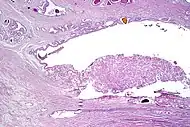

Intraductal adenocarcinoma | 2.8%[10] | ![]() H&E and CK5/6 |

|||||

Intraductal carcinoma

Intraductal carcinoma of the prostate gland (IDCP), which is now categorised as a distinct entity by WHO 2016, includes two biologically distinct diseases. IDCP associated with invasive carcinoma (IDCP-inv) generally represents a growth pattern of invasive prostatic adenocarcinoma while the rarely encountered pure IDCP is a precursor of prostate cancer.[19] The diagnostic criterion of nuclear size at least 6 times normal is ambiguous as size could refer to either nuclear area or diameter. If area, then this criterion could be re-defined as nuclear diameter at least three times normal as it is difficult to visually compare area of nuclei.[19] It is also unclear whether IDCP could also include tumors with ductal morphology.[19] There is no consensus whether pure IDCP in needle biopsies should be managed with re-biopsy or radical therapy. A pragmatic approach would be to recommend radical therapy only for extensive pure IDCP that is morphologically unequivocal for high-grade prostate cancer.[19] Active surveillance is not appropriate when low-grade invasive cancer is associated with IDCP, as such patients usually have unsampled high-grade prostatic adenocarcinoma.[19] It is generally recommended that IDCP component of IDCP-inv should be included in tumor extent but not grade.[19] However, there are good arguments in favor of grading IDCP associated with invasive cancer.[19] WHO 2016 recommends that IDCP should not be graded, but it is unclear whether this applies to both pure IDCP and IDCP-inv.[19]

- Intraductal carcinoma of the prostate with an infiltrative growth pattern may be morphologically difficult to distinguish from invasive cancer. One focus shows comedonecrosis (arrow), morphologically suggesting Gleason pattern 5 invasive carcinoma (a haematoxylin and eosin, b CK5/6)[19]

- Intraductal carcinoma of the prostate with very patchy basal cells identified by immunohistochemistry. At least some of the glands lacking basal cell immunoreactivity represent intraductal rather than invasive carcinoma (a haematoxylin and eosin, b CK 5/6)[19]